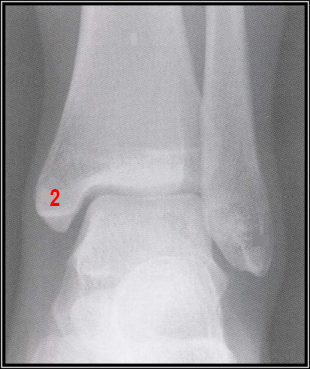

Mujer de 26 años de edad que acude a la consulta tras sufrir caída de su propia altura cuando caminaba a una fiesta; refiere inversión forzada del pie izquierdo. Durante la exploración física se observó aumento de volumen en la cara lateral del tobillo izquierdo y dolor localizado. Se diagnostica esguince del ligamento colateral externo de la articulación del tobillo. Se toma radiografía anteroposterior y lateral del tobillo. Se observó un trazo de fractura en la unión del maléolo lateral y la diáfisis de la fíbula.